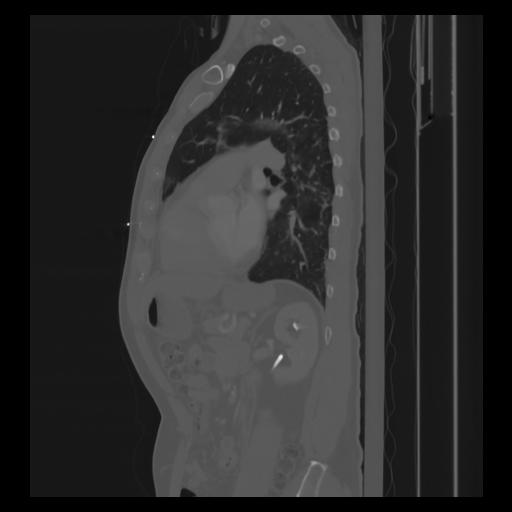

30 CUERPO,CE,Sagittal,3.000,CUERPO,Sagittal,